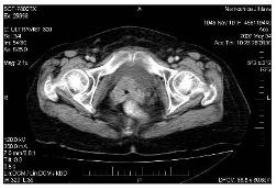

Pac. J. C., ročník 1946. V anamnéze Ebsteinova

anomálie plícnice, jinak bez komorbidit. V březnu 2006 léčena pro

epidermoidní karcinom děložního čípku pT1b pN0 M0 operací podle

Wertheima. V dubnu 2007 zjištěna lokální recidiva (obr. 1) a navíc

mnohočetné metastázy do plic (obr. 2).

Obr.1

Obr.2